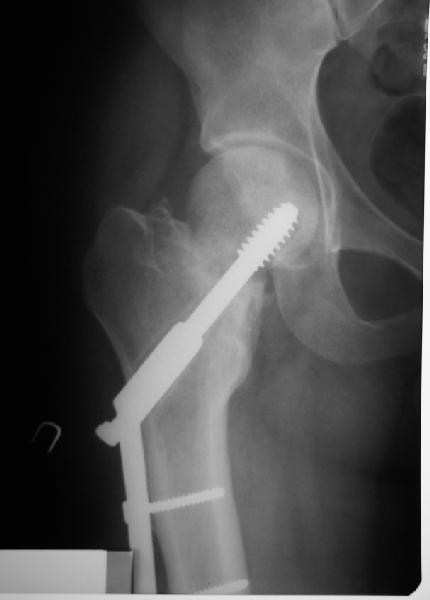

Учитывая возраст больного и качество кости, я однозначно за остеосинтез. Можно обойтись и без остеотомии, линия излома не вертикальная. Возможно с костной аутопластикой для стимуляции. Только отрепонировать хорошо, на представленных снимках, перелом недорепонирован, есть ротационное смещение. Плюс винт биомеханически введен не совсем удачно.

на представленных рентгенограммах прослеживается линия резорбции вокруг введенного винта, что свидетел ствует о нестабильности произведенного остеосинтеза ии отсутствии консолидации перелома. На мой взгляд нужно произвести ркт исследование и выполнить при отсутствии консолидации реостеосинтез с костной аутопластикой. При отсутствии сращения после данной операции остается ввариант с эндопротезированием. Выполнить репозицию несросшегося перелома закрытым способом на мой взгляд не совсем реально, открытая репозиция чревата аваскулярным некрозом. Выполнение вальгизирующей остеотомии считаю нецелесообразным так как это приведет к увеличению давления на головку (за счет натяжения мышц бедра )6 лишенную нормального кровотока приведет к ее коллабированию. С уважением Даниленко Олег.

Учитывая, что при первичном синтезе DHS репозиция, по всей видимости, была неадекватная, то открывая область перелома для репозии, можно получить аваскулярный некроз головки.

Уважаемые коллеги! мне кажется, что можно ввести в шейку дополнительно 1-2 спонгиозных компрессирующих винта параллельно опорному винту ДНС - его по видимому заклинило в втулке опорной пластины, что и послужило причиной несращения. Винты дадут дополнительную компрессию, стабилизацию и динамизацию. А протез всегда успеете.